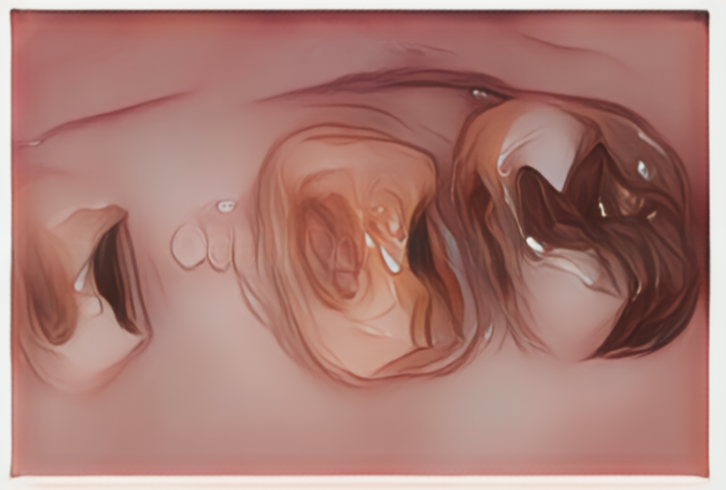

治療終了時の状態です。材質はセラミックを用いないジルコニアという材料(フルジルコニアクラウン)を選択して、ブリッジ修復を行いました。強度があり軽く、ここ数年でそれなりの色調表現も可能になりました。セラミック修復に比べるとやや透明感は劣りますが、割れたり欠けたりする可能性が大きく軽減できることがメリットです。また、セラミック修復に比べると削る量も少なくなるため、土台の歯にも優しい方法になります。さらにツルツルに研磨して仕上げることで、かみ合わせの相手の歯を磨耗させるリスクが最も少ない方法でもあり、現在は奥歯のかぶせ治療の第一選択と考えております。

フルジルコニアクラウン 11〜13.2万円/本(税込)

同様にフルジルコニアブリッジ修復を行った症例です。